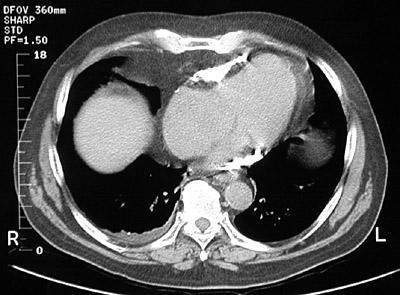

| The chest CT scan above shows a more advanced constrictive pericarditis with extensive bright calcification around the heart. In the lateral chest radiograph below, the calcification is best seen anteriorly. Such restriction of cardiac wall motion can produce heart failure. |